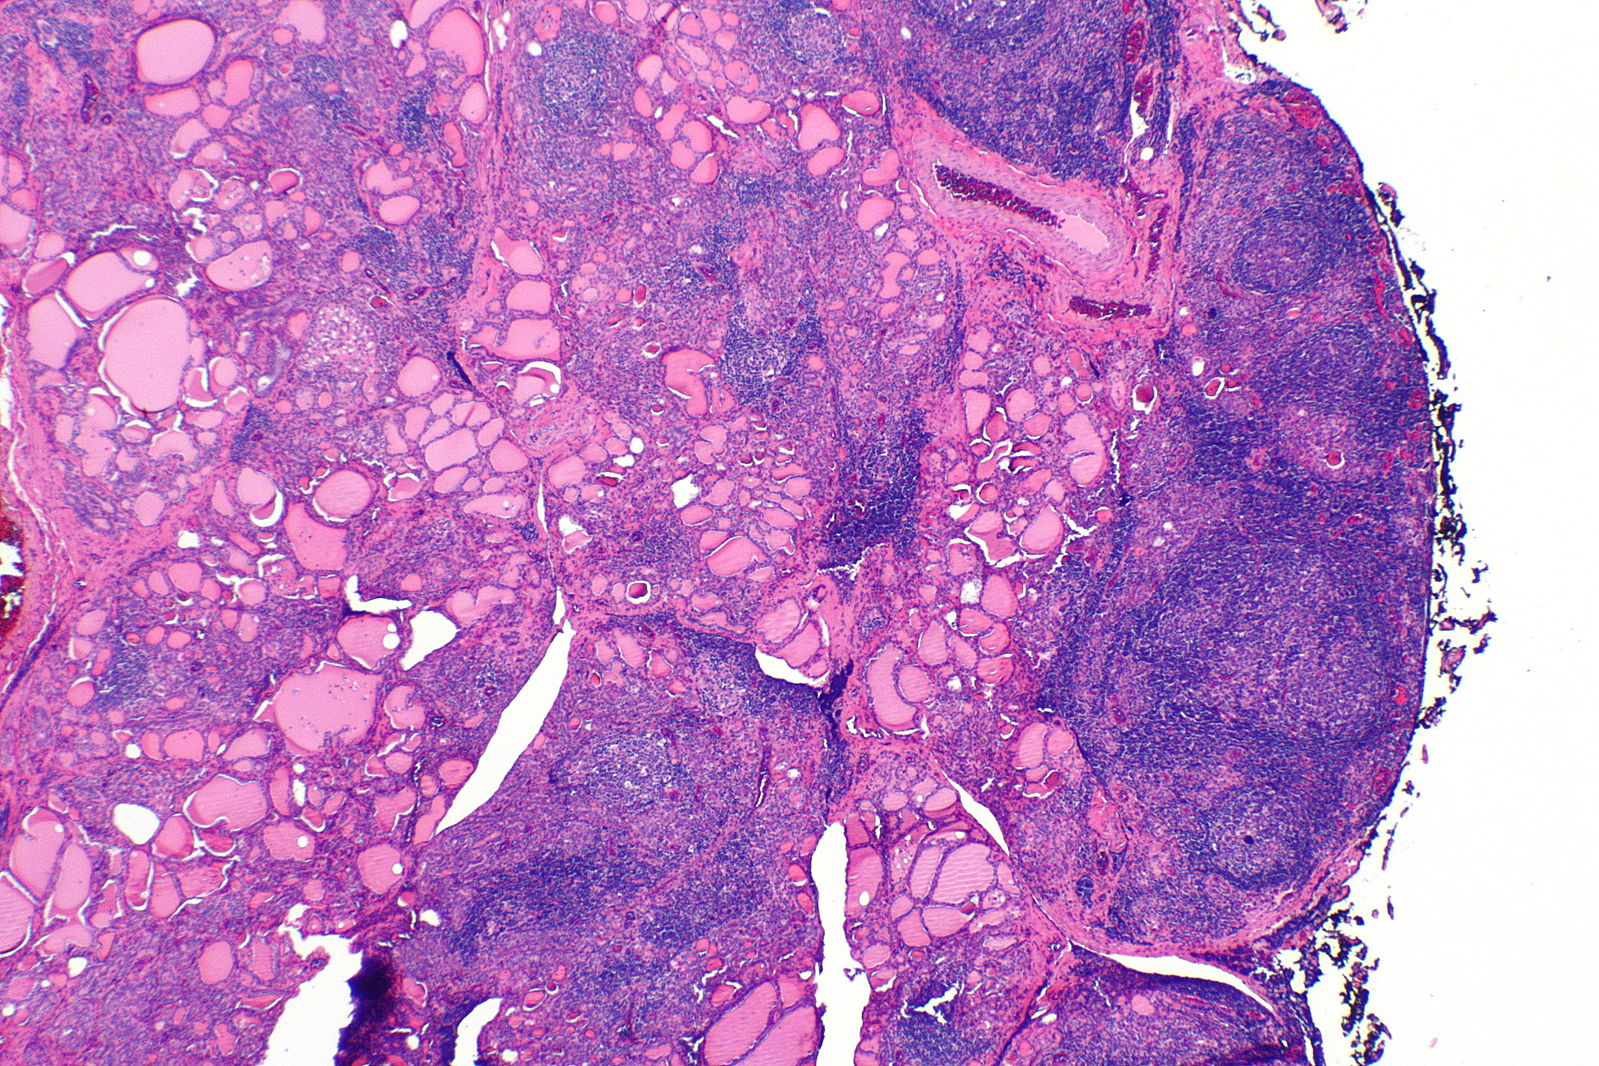

Hashimoto’s thyroiditis, also termed as chronic lymphocytic thyroiditis. It is the most common reason of hypothyroidism in the US. Hashimoto’s thyroiditis is an autoimmune disorder in which chronic inflammation is caused due to antibodies being directed against the thyroid gland. Hashimoto’s thyroiditis is most commonly seen in middle aged women, but can also be seen at any age, and can also influence children and men.

Hashimoto thyroiditis is a histologic diagnosis. A biopsy is required to diagnose Hashimoto’s thyroiditis.

Enlarged and firm

[6]Image credit: https://commons.wikimedia.org/wiki/File:Hashimoto_thyroiditis_-_alt_--_very_low_mag.jpg